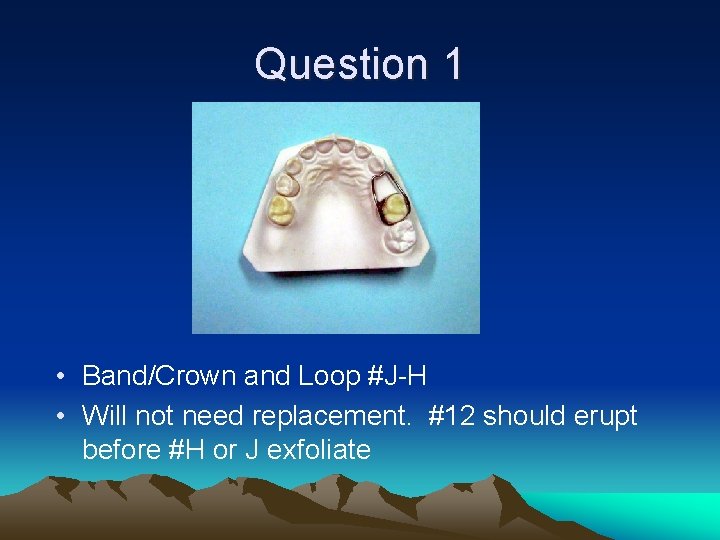

Question 1 • What tooth was extracted? How old is this child? • What is the appropriate space maintainer? • Will it have to be replaced with a different space maintainer in the future? If so, with what?

Question 1 • 5 or 6 y. o. child. Tooth #I extracted.

Question 1 • Band/Crown and Loop #J-H • Will not need replacement. #12 should erupt before #H or J exfoliate